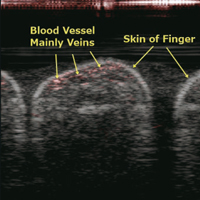

• Effect of amplifier gain on photoacoustic SNR (Signal to Noise Ratio) in an LED-based photoacoustic imaging system

Toshitaka Agano, Kunio Awazu

77-85

18-11-2020

https://doi.org/10.5978/islsm.20-OR-09